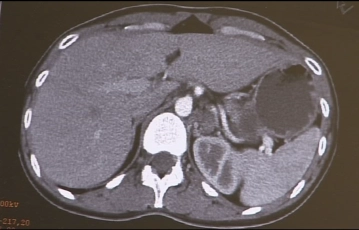

In der Bildbegung zeigt sich eine ca. 5-6 cm große multinodöse, zystisch imponierende Raumforderung im Bereich der linken Nebenniere, die klinisch als Phäochromozytom identifiziert wurde.

Computertomographischer Befund